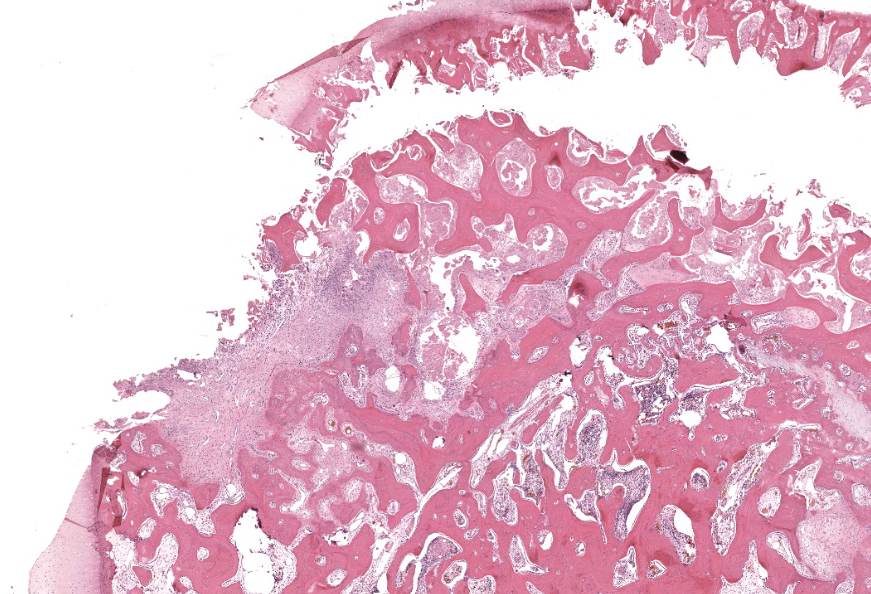

Femoral head: Affecting approximately 30-50% of the epiphysis from the subchondral aspect of the articular cartilage to the physis, there is a focally extensive area of osteonecrosis characterized by bony trabeculae which are irregular and brightly eosinophilic with loss of differential staining. There is loss of both osteocytes within lacunae and osteoblasts lining trabeculae in this region. Along the margins of the necrotic area, multiple bone trabeculae are fragmented and/or have scalloped margins with osteoclasts in Howship’s lacunae (osteolysis). The intertrabecular spaces within and at the periphery of the necrotic area contain variably amounts of amorphous eosinophilic matrix (fibrin), occasional neutrophils and macrophages and/or loosely arranged myxomatous to collagenous matrix with variable numbers of plump spindle cells and capillaries (fibroplasia). Occasionally, there are also finer, irregular trabeculae of paler staining or partially mineralized bone (woven bone). Adjacent viable trabeculae are lined by numerous active osteoblasts (remodeling) and are sometimes laced with wavy basophilic lines (resting / resorption lines). The articular cartilage is fragmented (likely artefact).Contributor's Morphologic Diagnoses:

Osteonecrosis, focally extensive, chronic with fibroplasia and bone remodeling; femoral head.Contributor's Comment:

Femur, epiphysis: Osteonecrosis, chronic, focally extensive, moderate, with osteolysis, woven bone, fibrosis, and bony remodeling.JPC Comment: